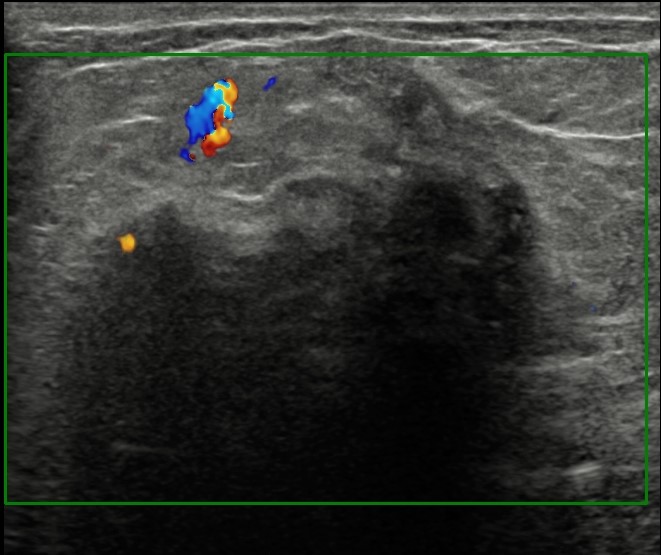

The most common cause of skin metastases in adult women is primary breast carcinoma, which comprises about 70% of cases [1]. Skin metastases have non-specific clinical appearances, making it challenging to differentiate them from other benign conditions [1]. We present a case of a 52-year-old female with type II diabetes and a three-month history of refractory skin lesions who did not respond to anti-inflammatory treatment. The patient subsequently complained of a right breast lump, evaluation of which led to the diagnosis of bilateral synchronous invasive lobular carcinoma.